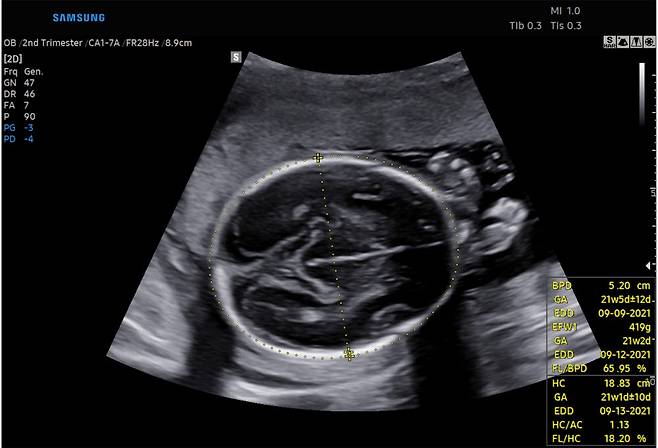

태아의 성장과 발육 상태를 빠르게 판단할 수 있는 '바이오메트리'와 태아의 심장 진단을 도와주는 '태아심장' 솔루션이 대표적이다.

'바이오메트리' 솔루션은 태아의 영상에서 머리, 배, 다리 등을 인식해 태아의 성장 정도를 측정해주며, '태아심장' 솔루션은 태아의 심장을 인식해 각 부위를 표시하고 측정해주는 기능을 구현한다.